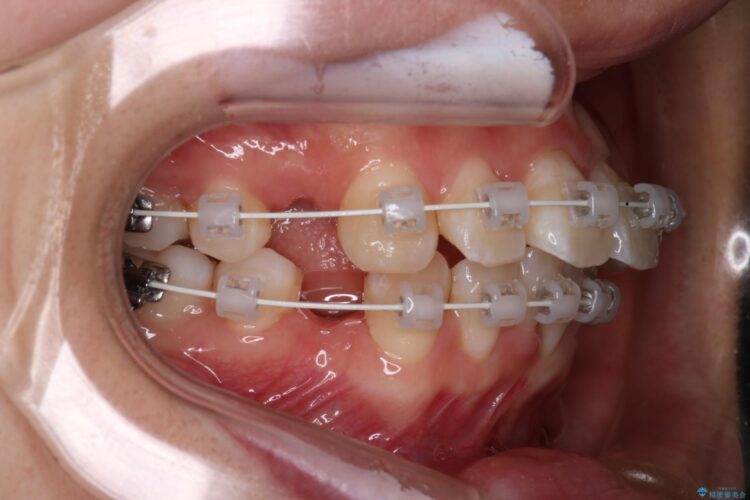

上下4番目の歯を抜歯してガタつきを改善しながら口元を下げる治療計画を立てました。

抜歯矯正で口元を下げたことで、Eラインが大変綺麗になりました。